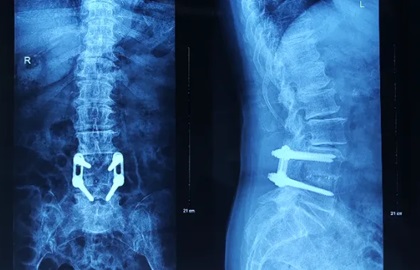

【医疗动态】跨越22年的医患情缘:闽澳专家联手为七旬澳门同胞解决“双重瘫痪”危机

一位执着的闽籍澳门老人,一组跨越世纪的骨科内植物,一台涉及两大脊柱节段的高难度手术——近期,黄播 骨伤科二区上演了一场惊心动魄的“神经保卫战”。